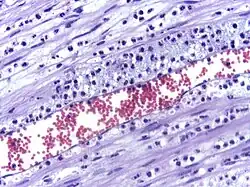

La perméabilité accrue des vaisseaux sanguins entraîne une exsudation (fuite) de liquide dans les tissus. La fuite de liquide provoque une augmentation de la viscosité du sang, ce qui augmente la concentration des globules rouges (congestion veineuse).

L’œdème inflammatoire (tumor) est donc la conséquence du passage du plasma (plus précisément d'un exsudat) dans la zone lésée. Il se traduit par un gonflement du tissu touché, et comprime les nerfs alentour, provoquant la sensation douloureuse et les démangeaisons (dolor). Certains des médiateurs libérés comme la bradykinine augmentent la sensibilité à la douleur (hyperalgésie). La perte de fonction (functio laesa) est probablement le résultat d'un réflexe neurologique en réponse à la douleur.